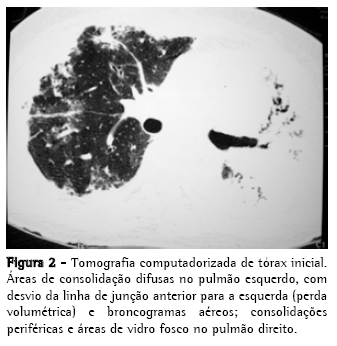

Radiograma e tomografia computadorizada de tórax iniciais, nas Figuras 1 e 2;

De um total de 12 casos relatados, cinco foram submetidos à tomografia de tórax.(4,17,18) Em quatro pacientes foram detectadas consolidações, em geral focais e de predomínio basal, em um paciente foi detectado derrame pleural e em um paciente foram descritos apenas nódulos peribronquiolares difusos. Não houve relatos de consolidações extensas. O pequeno número de pacientes não nos permite estabelecer um padrão, embora consolidações tenham sido encontradas em 80% dos pacientes.